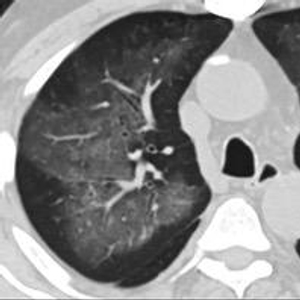

6天后的轴向CT平扫图像显示毛玻璃影变为实变和轻度结构扭曲。(同一病人CT影像)